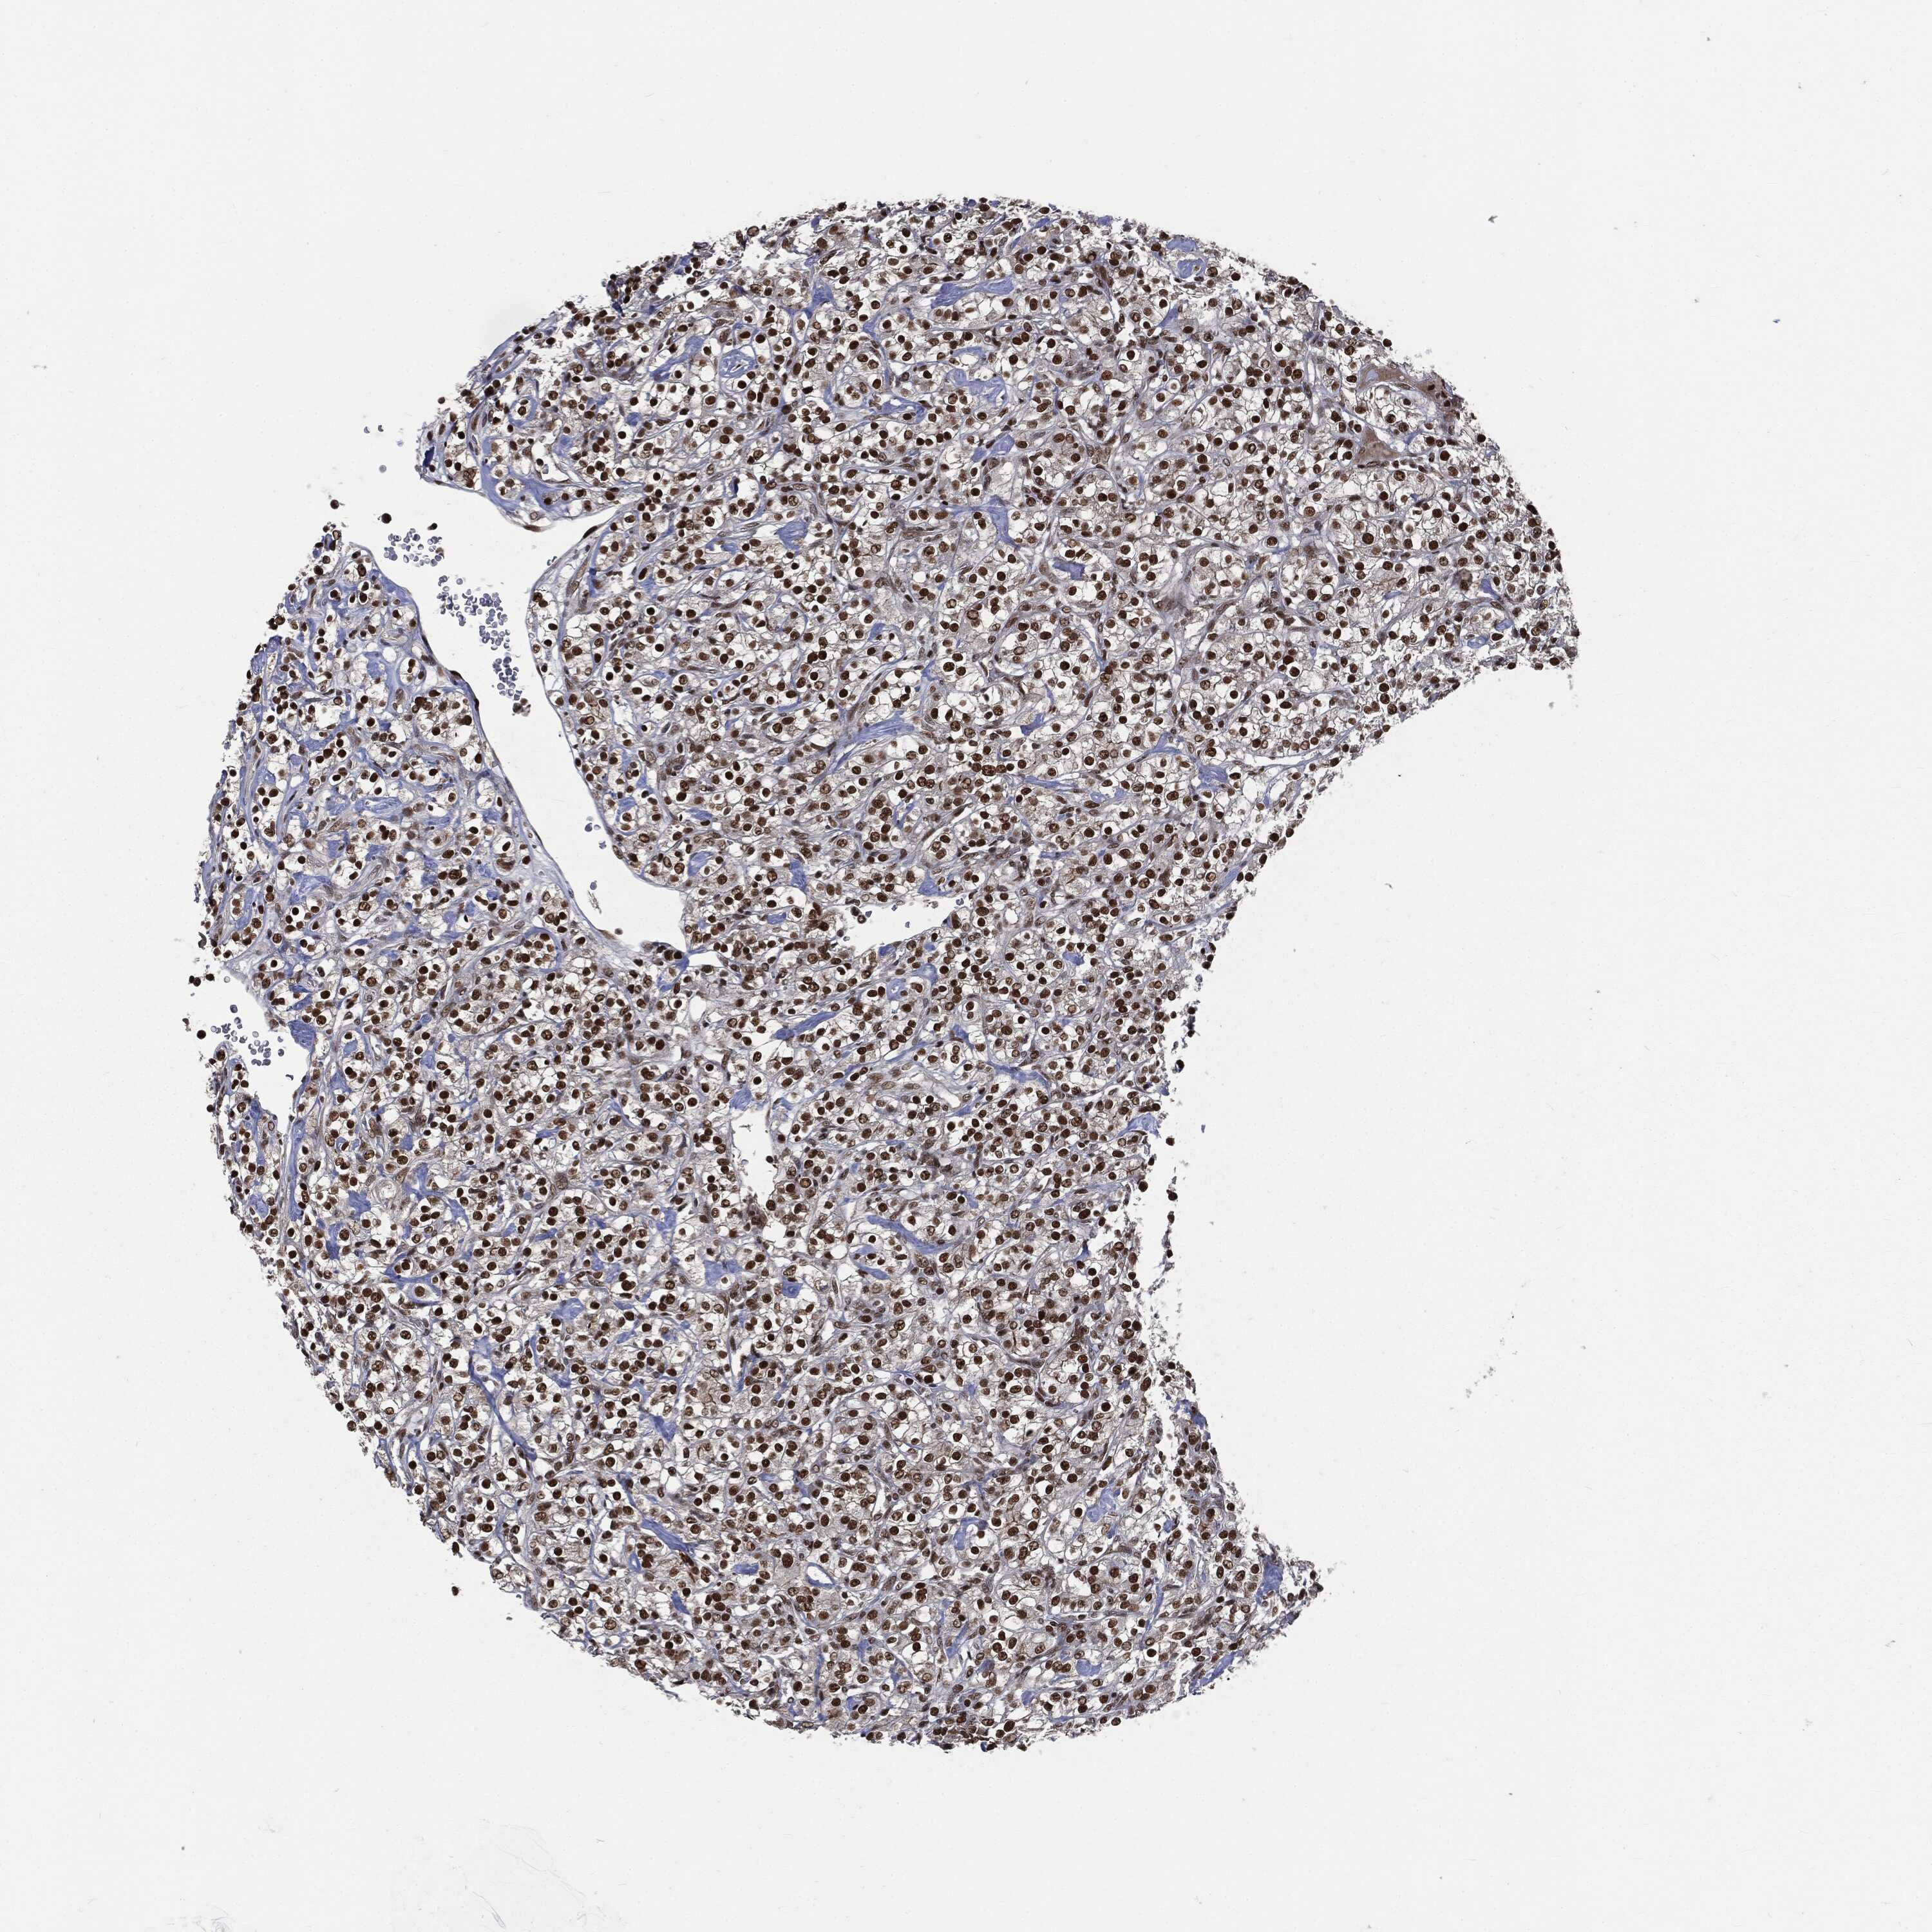

KIDNEY RENAL CLEAR CELL CARCINOMA (TCGA) - Interactive survival scatter ploti

The Survival Scatter plot shows the clinical status (i.e. dead or alive) for all individuals in the patient cohort, based on the same data that underlies the corresponding Kaplan-Meier plots. Patients that are alive at last time for follow-up are shown in blue and patients who have died during the study are shown in red.

The x-axis shows the expression levels (FPKM) of the investigated gene in the tumor tissue at the time of diagnosis. The y-axis shows the follow-up time after diagnosis (years). Both axes are complimented with kernel density curves demonstrating the data density over the axes. The top density plot shows the expression levels (FPKM) distribution among dead (red) and alive patients (blue). The right density plot shows the data density of the survived years of dead patients with high and low expression levels respectively, stratified using the cutoff indicated by the vertical dashed line through the Survival Scatter plot. This cutoff is automatically defined based on the FPKM cutoff that minimizes the p-score. The cutoff can be changed by dragging the vertical line or by entering a cutoff value in the square labeled "Current cut-off".

Under the Survival Scatter plot the p-score landscape (black curve; left axis) is shown together with dead median separation (red curve; right axis). Dead median separation is the difference in median mRNA expression between patients who have died with high and low expression, respectively. It is calculated as follows: median FPKM expression of dead patients with high expression - median FPKM expression of dead patients with low expression. This is intended to aid the user in visually exploring custom cutoffs and the associated p-scores and dead median separation.

Individual patient data is displayed and can be filtered by clicking on one or more of the category buttons on the top of the page. Categories describing expression level and patient information include: high, low, alive, dead, female, male and tumor stages. The scale of the x-axis can be toggled between linear and log-scale by clicking on the "x log" button. Mouse-over function shows TCGA ID, patient information and mRNA expression (FPKM) for each patient.

& Survival analysisi

Kaplan-Meier plots summarize results from analysis of correlation between mRNA expression level and patient survival. Patients were divided based on level of expression into one of the two groups "low" (under cut off) or "high" (over cut off). X-axis shows time for survival (years) and y-axis shows the probability of survival, where 1.0 corresponds to 100 percent.

DPH2 is not prognostic in Kidney Renal Clear Cell Carcinoma (TCGA)

Best expression cut offi

Based on the FPKM value of each gene, patients were classified into two groups and association between prognosis (survival) and gene expression (FPKM) was examined. The best expression cut-off refers the FPKM value that yields maximal difference with regard to survival between the two groups at the lowest log-rank P-value. Best expression cut-off was selected based on survival analysis .

When clicking on this number, the vertical dashed line indicating cut-off, the interactive survival plot, and the Kaplan-Meier curve will be adjusted to show results based on the best expression cut-off.

: 5.7

Median expressioni

Median expression refers to the median FPKM value calculated based on the gene expression (FPKM) data from all patients in this dataset. When clicking on this number, the vertical dashed line indicating cut-off, the interactive survival plot, and the Kaplan-Meier curve will be adjusted to show results based on the median expression.

: N/A

Median follow up timei

Median follow up time refers to the median time (years) after diagnosis with this type of cancer, based on clinical data from all patients in this dataset.

P scorei

Log-rank P value for Kaplan-Meier plot showing results from analysis of correlation between mRNA expression level and patient survival.

N/A

5-year survival highi

5-year survival for patients with higher expression than the expression cutoff.

For melanoma and glioma, 3-year survival is shown.

5-year survival lowi

5-year survival for patients with lower expression than the expression cutoff.

TCGA RNA samplesi

RNA-seq data is reported as average FPKM (number Fragments Per Kilobase of exon per Million reads), generated by the The Cancer Genome Atlas (TCGA) .

Normal distribution across the dataset is visualized with box plots, shown as median and 25th and 75th percentiles. Points are displayed as outliers if they are above or below 1.5 times the interquartile range. FPKM values of the individual samples are presented next to the box plot.

Average pTPM 8.2

Number of samples 521